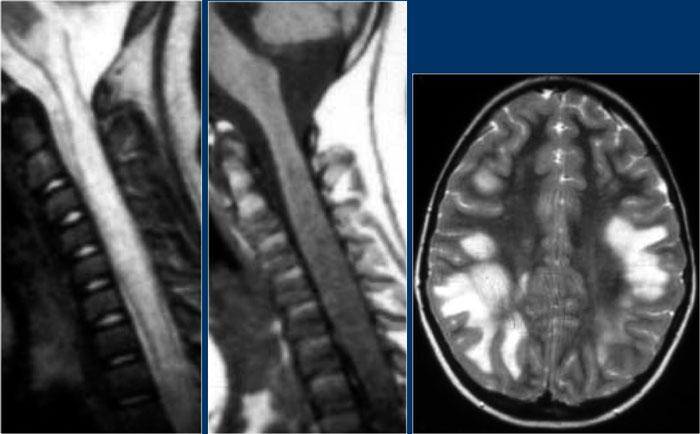

Ở một bệnh nhân khác có các tổn thương không đặc hiệu trong tủy sống.

Chỉ dựa vào khảo sát cột sống đơn thuần, chúng ta có một chẩn đoán phân biệt rộng.

Tuy nhiên khi khảo sát thêm não, sẽ rõ ràng rằng chúng ta đang đối mặt với MS.

Tiếp tục xem các hình ảnh của não.

Trong trường hợp này, các hình ảnh trên não rất hữu ích.

Vị trí của các tổn thương rất điển hình: cầu não, quanh não thất và dưới vỏ não.